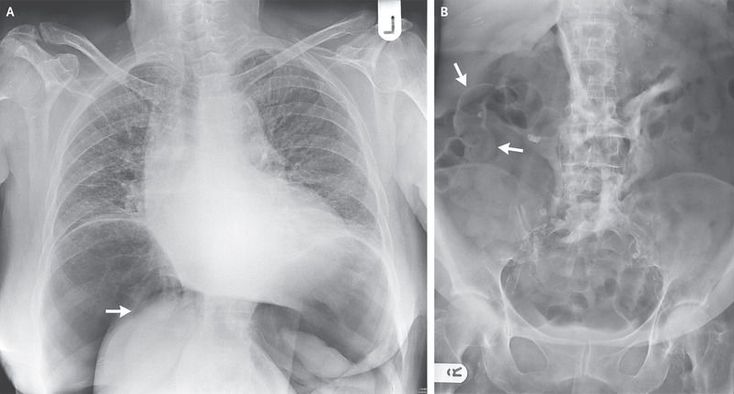

A previously well 76-year-old woman underwent elective colonoscopy for the investigation of persistent rectal bleeding and abdominal pain. The procedure was prolonged owing to the presence of a redundant sigmoid colon, and considerable manipulation was required in order to advance to the cecum. After the procedure, sudden abdominal distention developed, with signs of peritoneal irritation. A chest radiograph obtained while the patient was in the upright position showed a tension pneumoperitoneum with medial displacement of the liver (Panel A, arrow), raising concern about torsion of vessels in the porta hepatis. A radiograph of the abdomen showed Rigler's sign — air on both sides of the bowel, indicative of intraperitoneal gas (Panel B, arrows). The patient underwent urgent laparotomy, with Hartmann's resection for a large tear in the sigmoid colon. The patient was well at the follow-up visit 2 months after surgery, with a planned reversal of Hartmann's procedure.